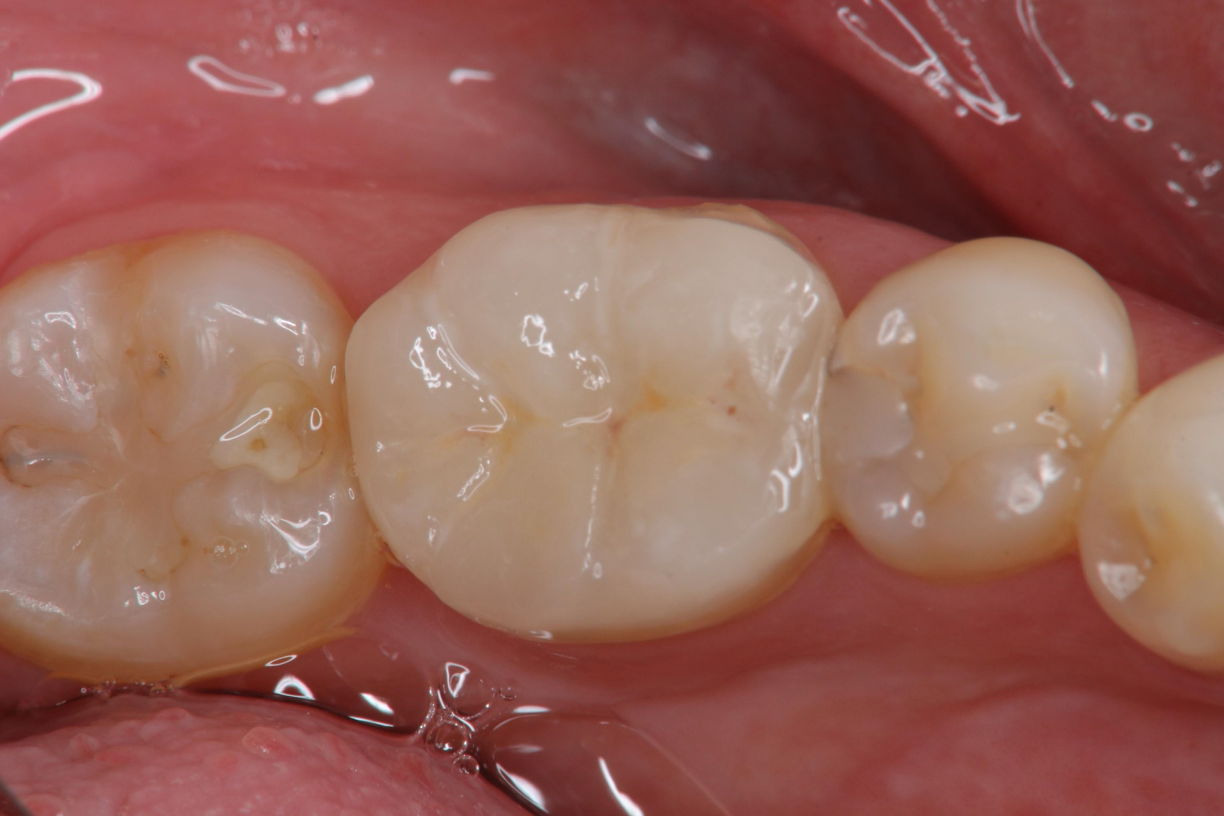

治療後,口內照相追蹤

根尖片顯示邊緣密接良好